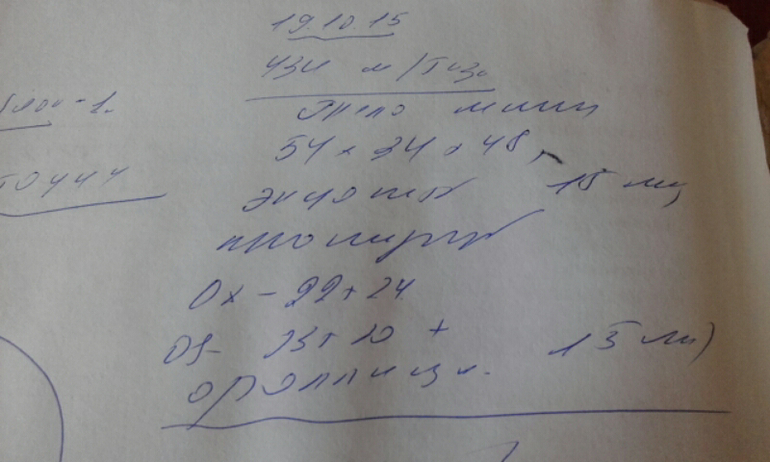

Девочки..я в шоке..вчеоа была на узи..ДФ 15 мм..Сегодня днем тест на О..Пока отрицательный..Но в предыдущие дни был вообще пустой..Сейчас пришла с приема от другог врача..Во первых даже не сделала осмотр..Во вторых даже толком снимки не смотрела и сказала что это все бред..ДФ нет и О не будет..Я расстроена это мягко сказать..Я в шоке...Прием длился 5 минут..

По снимку похоже на дф.какая киста...все хорошо.просто мне показалось что ниже написано про эндометрий...а так конечно теститесь думаю дня через 2 3 овуля

Эндометрий 15?я не ошиблась?

Это у нас такие врачи..эндометрий 8 мм

и эндометрий нормальный